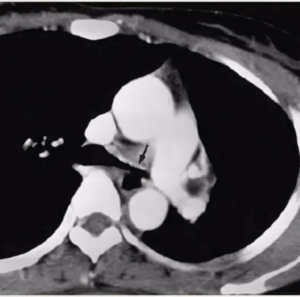

• obtained at level of right middle lobar bronchus

shows a right upper lobe airspace opacity adjacent to the trachea.